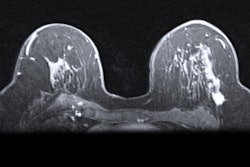

The most popular AI use cases included bone age prediction (9 sites), lung nodule detection on CT (8 sites), and stroke -- left ventricle occlusion (LVO) or intracranial hemorrhage detection on CT and CT angiography (8 sites).